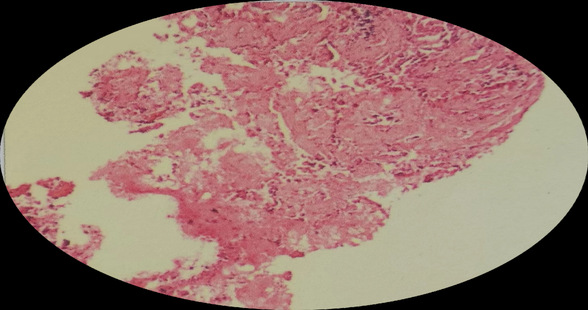

术后病理